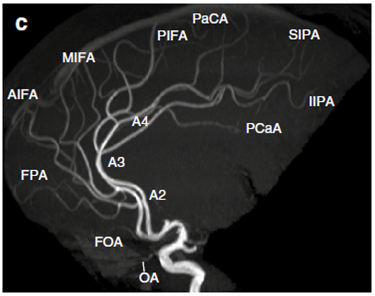

Intracranial vessels

Middle

cerebral artery

(From Neurovascular imaging –

2011)